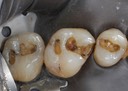

Joe Cha #18 amalgam removal

Joe Cha #18 prep